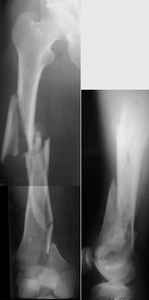

Attached are few examples from our Hospital:

A. Difficult reductions, even in retrograde nailing (my preference, easier control of "small" distal fragment) and it is much, much harder to do it anterograde (Alex, do you have one good case in your collection of anterograde nailing in very distal fractures - as you have suggested that I

should have done it in my previously posted case?

Malpositioning is much too common (recurvatum, varus - valgus).

B. Fixation loosening: distal cutting of the nail, non-unions do happen (cases attached).

Locking Plating has more distal screws than any nail, fixed angles and provides much better fixation, especially in osteoporotic bone.